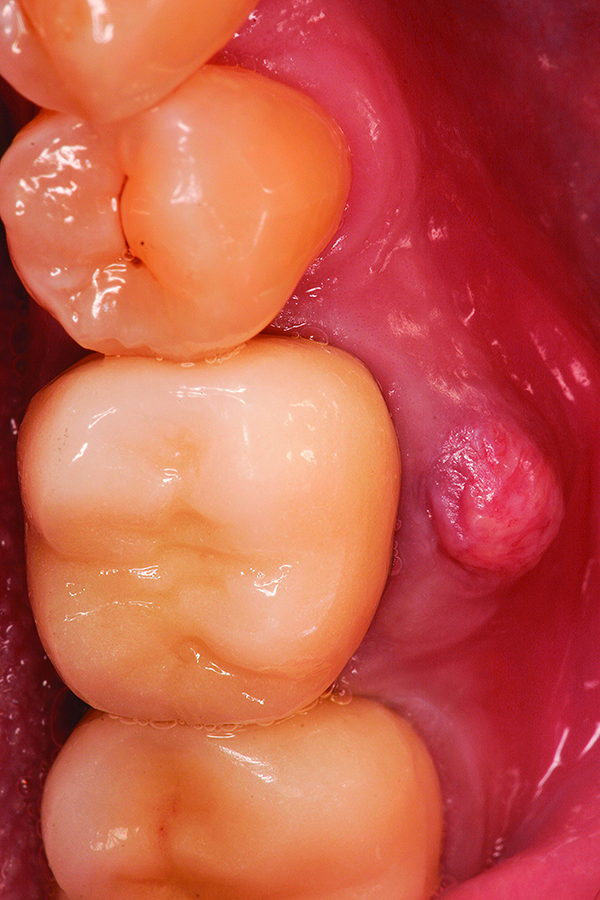

Fig 5. Healed bony ridge at 14 weeks following site preservation.

Figure 5

Fig 6. Placement of dental implants into healed bone. Note complete circumferential bone surrounding all aspects of the dental implants.

Figure 6